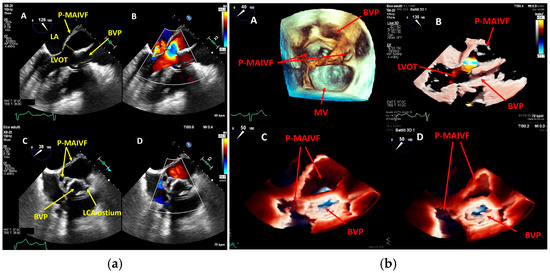

Multimodality Imaging in Infective Endocarditis: A Clinical Approach to Diagnosis

by Leonardo Brugiatelli, Francesca Patani, Carla Lofiego, Martina Benedetti, Irene Capodaglio, Pongetti Giulia, Francioni Matteo, Paolini Enrico, Nazziconi Marco, Kevin Maurizi, Furlani Giulia, Massari Arianna, Luciani Simone, Anselmi Benedetta, Gatti Chiara, Schicchi Nicolò, Fogante Marco, Tarsi Giovanni, Dello Russo Antonio, Di Eusanio Marco, Marini Marco and Fabio Vagnarelliadd Show full author list remove Hide full author list

Medicina 2025, 61(12), 2241; https://doi.org/10.3390/medicina61122241 - 18 Dec 2025

Infective endocarditis (IE) is a life-threatening condition with a rising incidence, demanding rapid and precise diagnosis. While echocardiography remains the cornerstone of initial evaluation, its limitations in complex cases—such as those involving prosthetic valves or cardiac devices—are well-known. This review synthesizes current evidence [...] Read more.

Infective endocarditis (IE) is a life-threatening condition with a rising incidence, demanding rapid and precise diagnosis. While echocardiography remains the cornerstone of initial evaluation, its limitations in complex cases—such as those involving prosthetic valves or cardiac devices—are well-known. This review synthesizes current evidence and guidelines to outline a practical, multimodality imaging approach for IE. We emphasize that integrating advanced techniques like cardiac computed tomography (CT) and [18F]-fluorodeoxyglucose positron emission tomography/computed tomography (FDG PET/CT) early in the diagnostic pathway, particularly in high-risk scenarios, significantly enhances diagnostic certainty, guides therapeutic decisions, and improves patient outcomes. A tailored imaging strategy, driven by clinical presentation and integrated within a multidisciplinary endocarditis team, is paramount for modern IE management. Full article

(This article belongs to the Special Issue Diagnosis and Treatment of Valvular Heart Diseases)

Show Figures

Figure 1